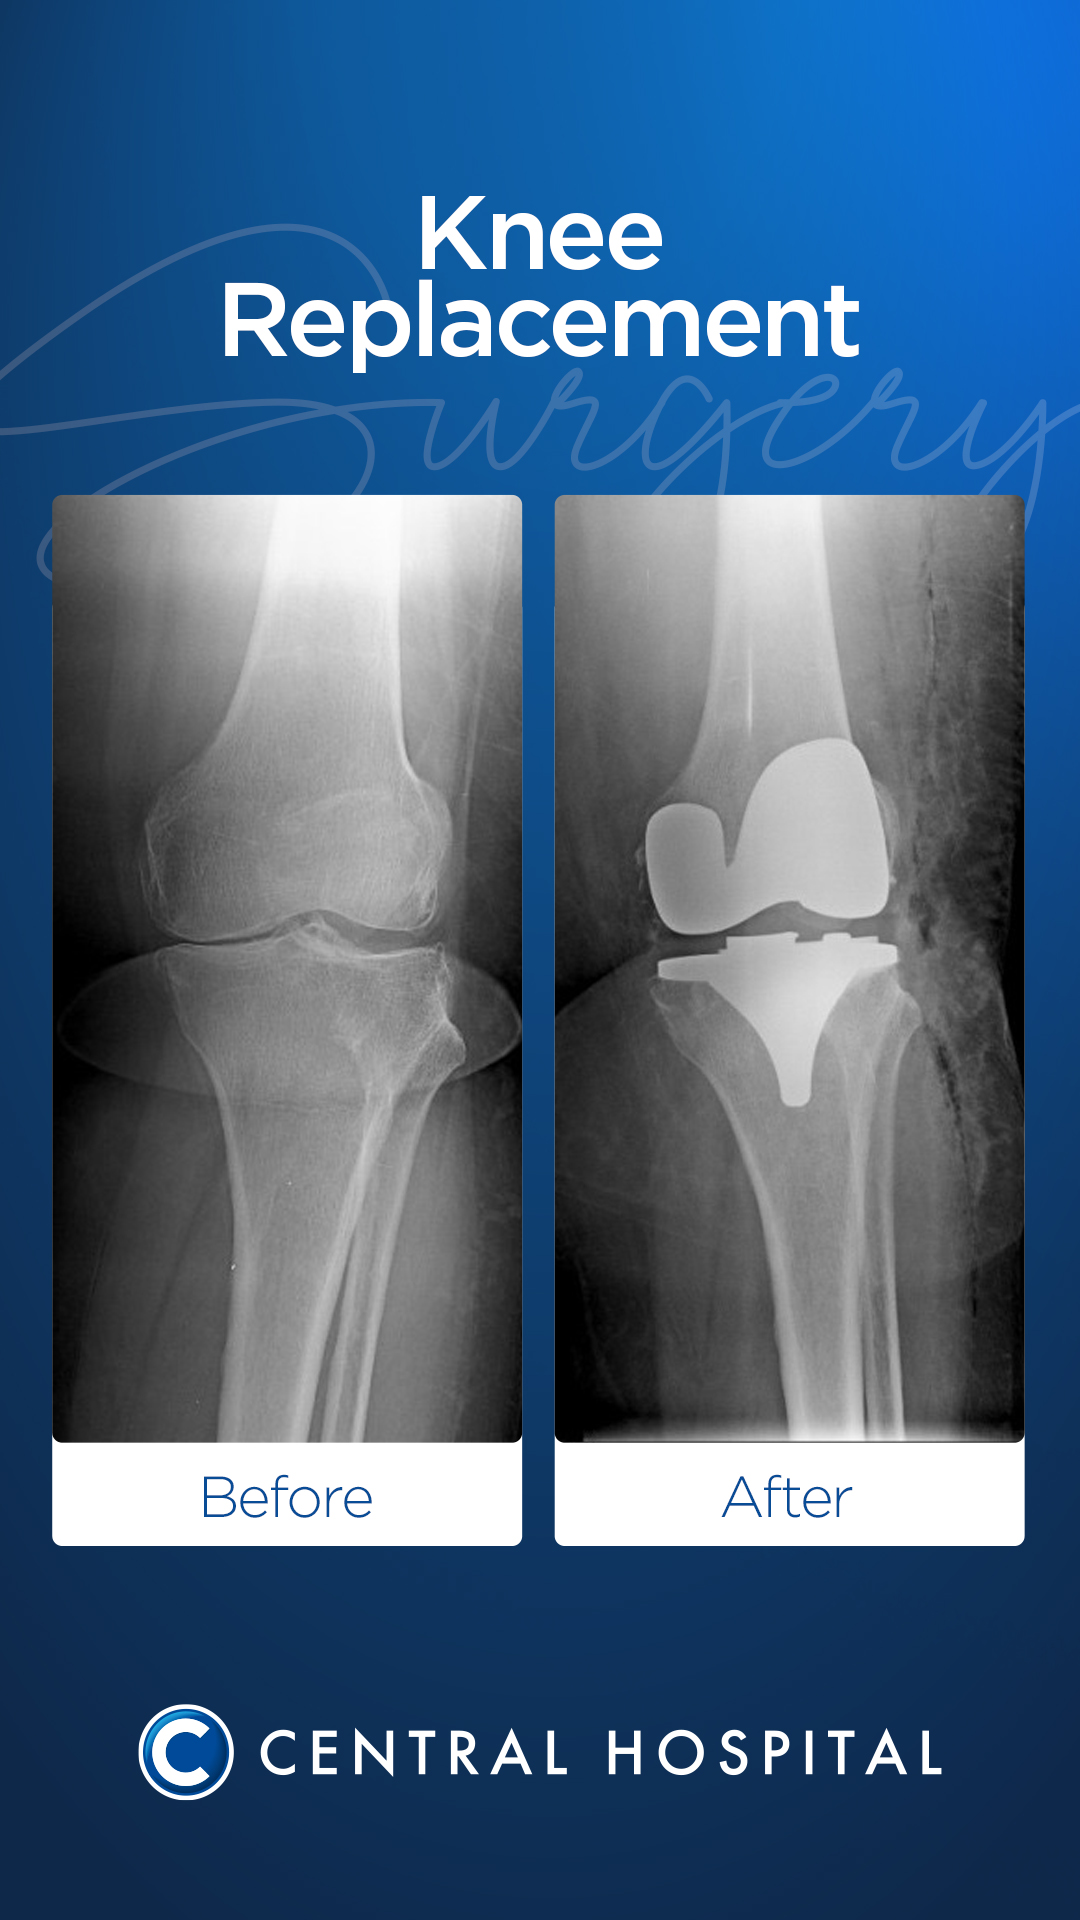

Cirugía de prótesis de rodilla

Durante la operación, las superficies articulares desgastadas y dañadas se limpian cuidadosamente, dejando en su lugar un inserto artificial (prótesis) hecho de metal o aleaciones plásticas especiales. Esta planificación quirúrgica se realiza de forma individual según la edad, el nivel de actividad y la estructura ósea del paciente.